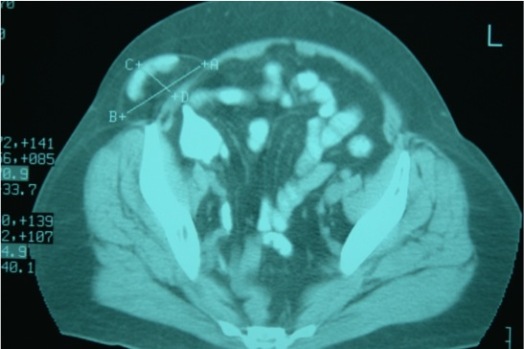

Imagen núm. 2: Tac abdominal con visión de la hernia de Spiegel y su contenido.